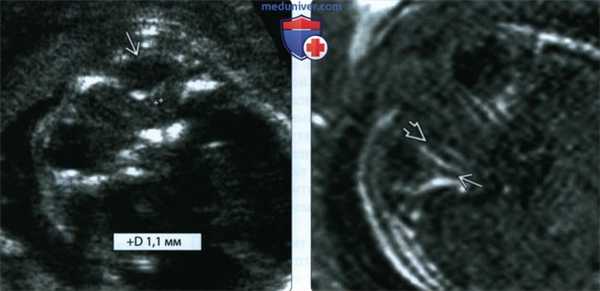

(Слева) При УЗИ глазницы в косой плоскости, проходящей через глазное яблоко, виден зрительный нерв в оболочке (маркеры). На 32-й неделе гестации диаметр в 1,1 мм меньше нормы, что позволяет предположить у плода с отсутствующей ППП гипоплазию зрительного нерва.

(Справа) При МРТ на Т1-ВИ на срезе, проходящем через глазницу, визуализируется нормально сформированный зрительный нерв (в отличие от комплекса зрительного нерва и его оболочки, различимых при УЗИ) в жировой ткани глазницы. Как показывает опыт, размер нерва должен примерно совпадать с размером внешних мышц глазного яблока. При проведении МРТ по поводу отсутствия ППП всегда необходимо исследовать зрительные нервы.